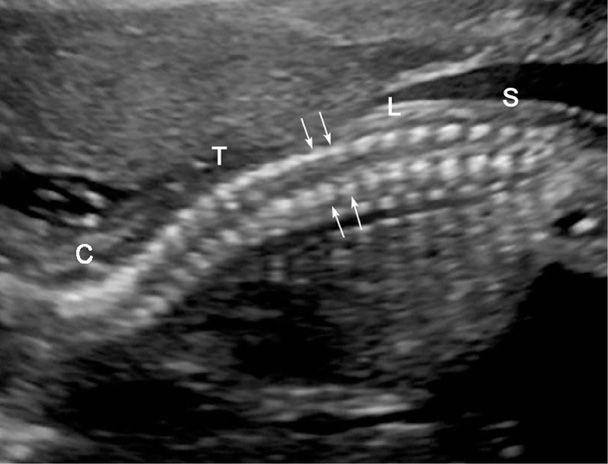

Baby spine Sonography, Ultrasound, Pediatrics